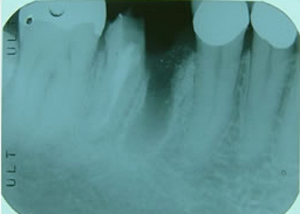

右下

第一第臼歯近心根破折

(大臼歯は歯根が二つに分かれている)

1.H18.4.12

抜歯後

(某歯科医院にて手前の歯根のみ抜歯)

2.インプラントする前

(抜歯後4ヶ月弱)